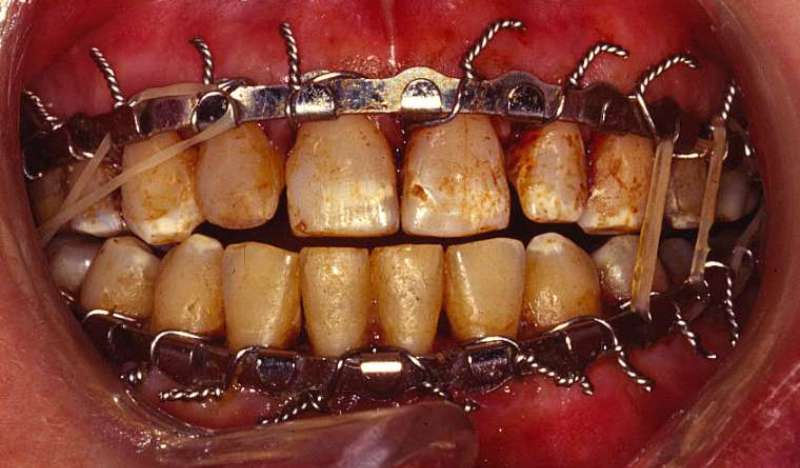

Шинирование

Данный метод заключается в фиксации поврежденной челюсти с помощью шин, которые могут быть выполнены из пластика или металла. Этот подход был разработан еще в прошлом столетии и продолжает применяться в современной медицине. С тех пор материалы, используемые для изготовления шин, претерпели значительные изменения. В настоящее время врачи используют ленточные и алюминиевые шины.

Тип шины, которую накладывают, зависит от степени травмы. В зависимости от результатов диагностики конструкция может быть установлена с одной стороны (если повреждена только одна челюсть) или с обеих сторон (при двойном переломе нижней челюсти). Если состояние зубов удовлетворительное, достаточно будет гибкой шины. Однако в случае, если трещина обнаружена в нескольких местах, потребуется более прочная конструкция, то есть металлическая. При ее установке также применяются крючки и кольца для надежной фиксации.